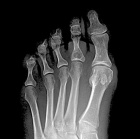

J.F. – 55 year old woman c/o left second toe pain for nearly three months after stubbing her toe.

Pain is dull, worse with activity. NSAIDs effective.

Zoom image: Radiological image Radiological image.